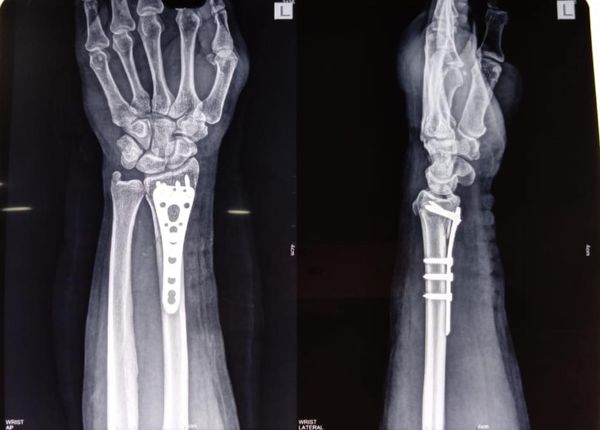

Most wrist fractures are treated with simple plaster cast, but in some cases like this one fracture involves the joint itself, in such a case unless absolute reduction of the joint line is achieved, the wrist and in turn hand may suffer severe loss of function.

Think of it in this way, would a door hinge work if it is even slightly bent out of shape? This surgery also helps in early mobilisation of wrist and hand which is a boon for a young patient such as this one